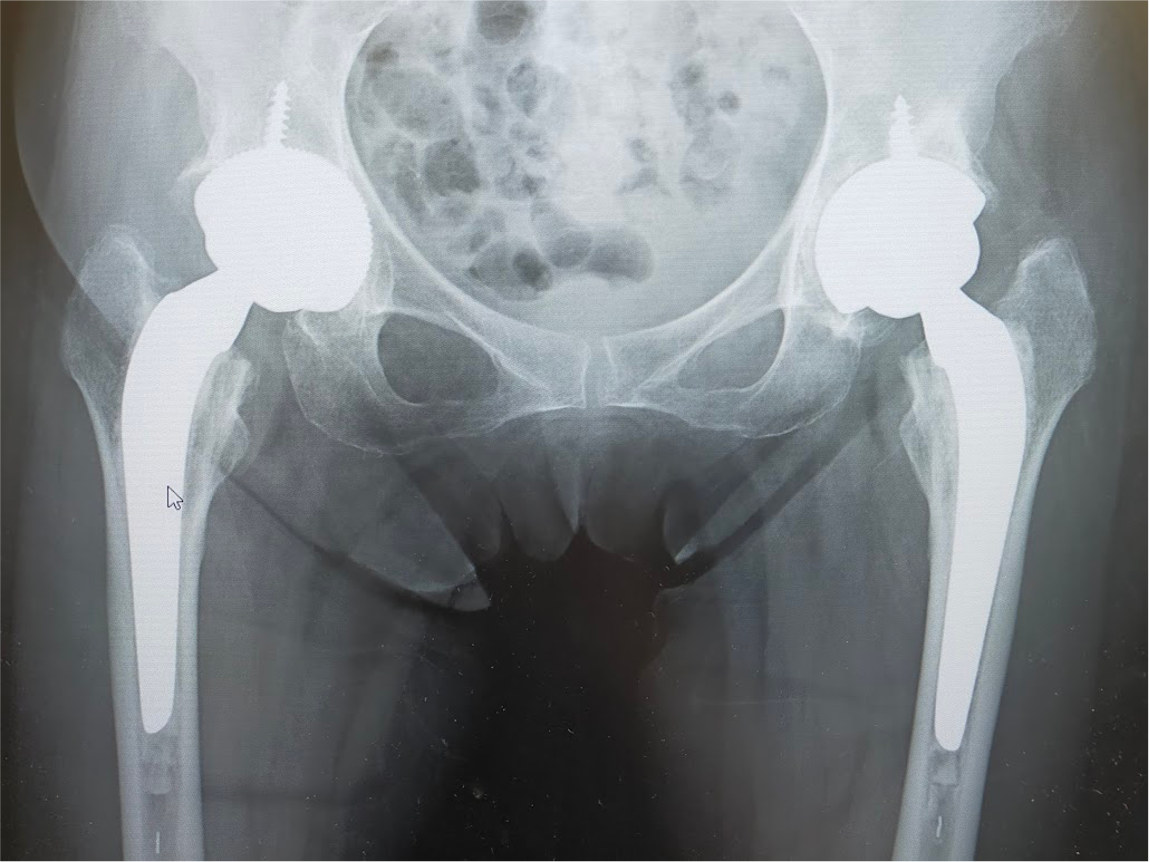

当院にて両側の人工股関節全置換術(THA)を施行。アプローチはAMIS(前方最小侵襲手術)で行い、術中に神経ブロックを併用することで、術後の疼痛コントロールを行い、術翌日から離床、リハビリを進めることができました。術後すぐに歩けることに本人も驚いていました。また、術後は一切の肢位の制限も行っていません。

〈手術後のレントゲン〉(正面)